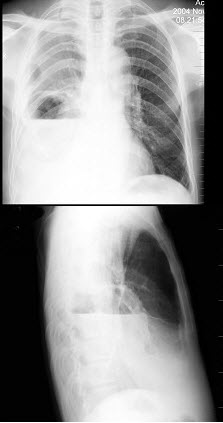

47、单项选择题

男,6岁。经常咳嗽、憋喘,呼吸急促、口唇青紫,进行性加重。X线检查如图,最可能的诊断为()

A.先天性PDA

B.先天性VSD

C.先天性ASD

D.法洛氏四联症

E.先天性肺动静脉瘘